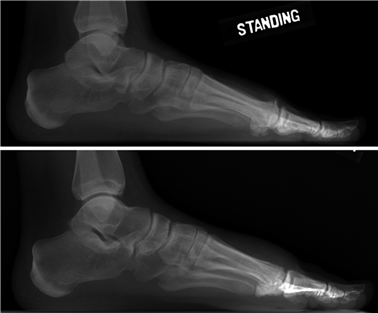

Weight-bearing anteroposterior (AP), lateral, and sesamoid axial radiographs are mandatory. On the AP view, the surgeon measures the Hallux Valgus Angle (HVA, normal < 15°), the Intermetatarsal Angle (IMA, normal < 9°), and the Distal Metatarsal Articular Angle (DMAA). The lateral view is scrutinized for Meary's angle (talo-first metatarsal angle) to identify midfoot collapse, as well as the presence of dorsal osteophytes indicative of hallux rigidus. The sesamoid axial view is critical for assessing the degree of sesamoid subluxation and the integrity of the crista.

Image